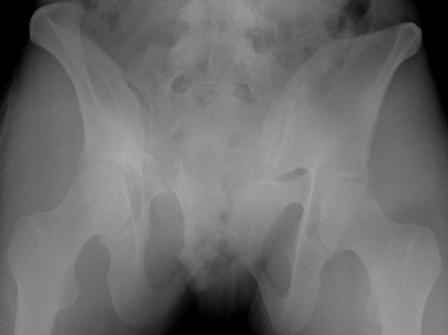

Серия до- и послеоперационных снимков этой пациентки. Хотя бы post factum обсудить. Не знаю, что можно сделать с задними отделами стержневым аппаратом, но три крепких парня открытым путем с помощью "волшебных" слов еле-еле смогли отрепонировать - сзади все было очень ригидно!

Здравствуйте, Евгений! У меня видна только дооперационная проекция inlet.